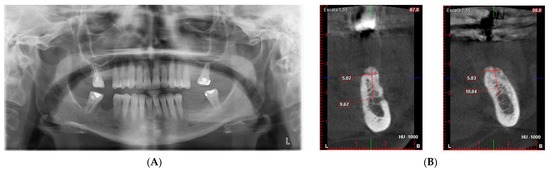

Rapoartele clinice documentate descriu mesh-ul de titan ca o structură concepută în primul rând pentru a stabiliza materialul de augmentare. Într-un caz clinic care a evaluat o mesh personalizată realizată digital, reconstrucția unui defect vertical și orizontal în mandibula posterioară a produs, după șapte luni, o creștere osoasă de 1,8 – 1,9 mm în lățime și 3,8- 4,2 mm în înălțime, confirmată histologic prin prezența unui os bine organizat. Autorii atribuie aceste rezultate modului în care bariera a reușit să mențină spațiul pe toată durata vindecării, limitând compresia materialului de augmentare în fazele inițiale.

Aceste observații punctuale sunt completate de datele extrase din studiile clinice și analizele mai extinse dedicate plaselor din titan. În evaluările în care au fost analizate reconstrucții verticale, orizontale și combinate, mesh-urile din titan au fost asociate cu creșteri osoase medii în jurul valorii de 4,3 mm pe direcția orizontală și 4,11 mm pe direcția verticală, rezultate obținute în contexte clinice variate și confirmate prin măsurători radiologice postoperatorii. Aceste valori reflectă capacitatea barierei de a menține un spațiu stabil chiar și în defecte extinse, unde presiunea țesuturilor moi reprezintă un factor limitativ.

sursa foto: Materials 2022, 15(18), 6271